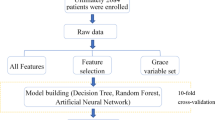

This study collected data for a total of 437 consecutive patients (199 with ICM and 238 with DCM) from the First Affiliated Hospital of Guangxi Medical University. The included patients were diagnosed with HF according to recently published guidelines [1]. All patients underwent invasive coronary angiography for diagnosis of ICM or DCM. DCM was defined as LV or biventricular contractile dysfunction and dilatation, rather than the presence of severe coronary artery disease and abnormal loading conditions. The diagnosis of dilated cardiomyopathy was confirmed after a systematic diagnostic procedure based on the definition of dilated cardiomyopathy published by the World Health Organization/International Society and Cardiology Federation and the latest Guidelines of China [19,20,21]. The diagnostic requirements were: (1) left ventricular ejection fraction (LVEF) decreased by < 45%, and left ventricular short axis shortening rate (LVFS) decreased by < 25%; (2) the left ventricular end diastolic volume or diameter of the standard map adjusted by body surface area and age was > 2 standard deviations (SDs) compared with the normal value; and (3) coronary angiography was used to evaluate coronary artery disease (CAD). However, even in the presence of CAD, the diagnosis of DCM can still be considered when the severity of HF is not proportional to the degree of CAD [22]. The inclusion criteria for ischemic cardiomyopathy were as follows: (1) history of symptomatic HF (New York Heart Association Functional grade II or higher) and a decrease in the LVEF by < 40% and (2) one or more of the following: a history of myocardial infarction or revascularization (coronary artery bypass graft or percutaneous coronary intervention), or with stenosis of 75% or more in the left main stem or left anterior descending artery, or with greater than 75% stenosis in two or more epicardial vessels [3, 20, 23]. To avoid influencing the results of the study, 38 patients with LVEF of 40–45% were excluded, and patients with missing echocardiographic and coronary angiographic data or with congenital heart disease, acute or sub-acute myocarditis, hypertrophic cardiomyopathy, primary valvular disease [24], infiltrative disease, restrictive cardiomyopathy, incomplete myocardial densification, infiltrative disease, and/or evidence of immune-mediated disease were excluded from this study. Ultimately, the study group consisted of 399 patients (199 with ICM and 200 with DCM). Figure 1 shows the patient selection and modeling process. This study was approved by the Ethics Committee of First Affiliated Hospital of Guangxi Medical University and was conducted according to the principles defined in the Declaration of Helsinki. Written informed consent was obtained from all individual participants included in this study.

Machine learning workflow for differentiation of ICM and DCM. A machine learning model was developed to differentiate between ICM and DCM. The machine method included feature selection using a statistical method and 10-fold cross-validation, and 4 different algorithms were compared. ICM: ischemic cardiomyopathy; DCM: dilated cardiomyopathy